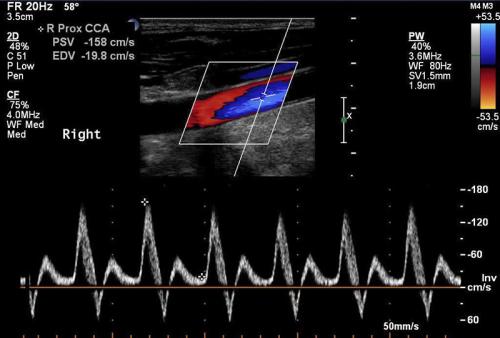

Doppler USG ürolojide en sık erektil Disfonksiyon (ereksiyon olamama, penis sertleşmesi sorunları, impotans) durumunda, nedenin ara...